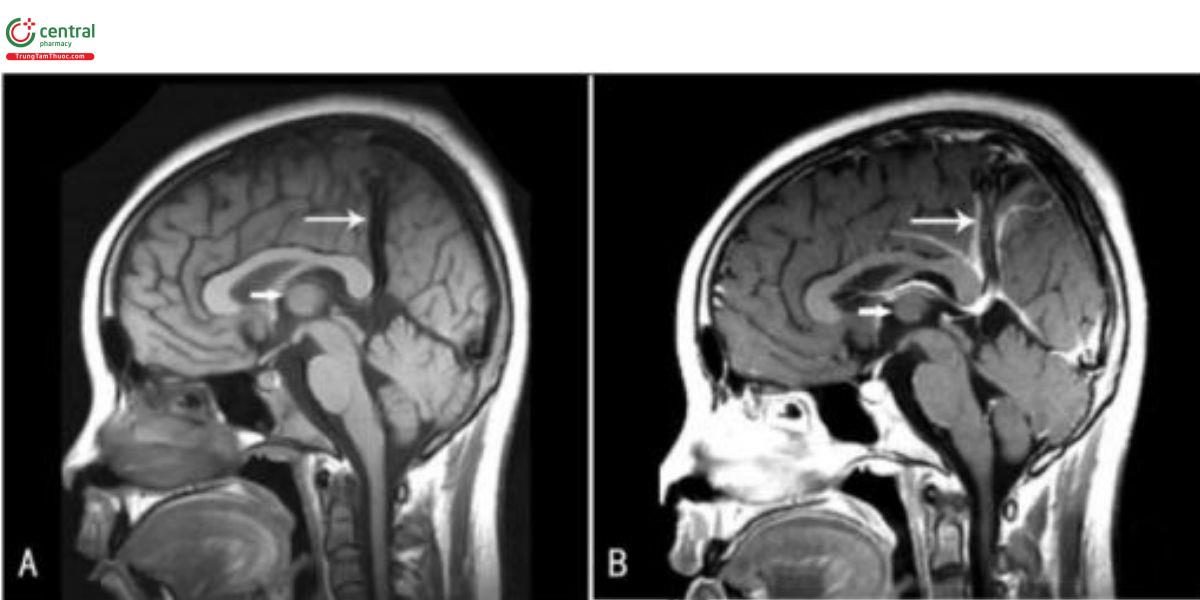

Sự tồn tại dai dẳng của đường rò động tĩnh mạch giữa các mạch mạc đám rối nguyên thủy và tỉnh mạch trung não trước (MProsV) là cơ chế bệnh sinh chủ yếu của VGAM, xảy ra từ tuần thứ 6 đến tuần thứ 11 của thai kỳ, sau khi vòng tuần hoàn Willis được hình thành (Hình 1). Phần sau của MProsV sẽ tồn tại và phát triển thành tĩnh mạch Galen, trong khi phần trước thoái triển song song với quá trình hình thành các tĩnh mạch não trong. Phần còn lại của MPros V sau đó kết nối với các tĩnh mạch nào trong để tạo thành tĩnh mạch Galen, và điều này có thể dẫn đến sự tồn tại của kết nối giữa VGAM và hệ tĩnh mạch sâu. Raybaud và Strother là những người đầu tiên xác định cầu trúc tĩnh mạch giản này chính là MProsV. Kết nối động tĩnh mạch giữa các mạch mạc đám rối nguyên thủy và MProsV gây ra những bất thường huyết động, dẫn đến cản trở quá trình thoải triển sinh lý của tĩnh mạch phôi và sự hình thành tĩnh mạch Galen. Sau đó, sự kết nối động tĩnh mạch có lưu lượng cao làm tăng áp lực tĩnh mạch và gây giân phình MProsV. Ngoài ra, hẹp các xoang màng cứng cũng là một nguyên nhân khác gây giãn, do dòng chảy nhanh và xoáy mạnh tạo ra bởi kết nối động tĩnh mạch.

Sự dẫn lưu của dị dạng hướng về xoang thẳng, và cũng có thể dẫn lưu vào xoang dọc trên thông qua xoang liểm tổn tại, trong trường hợp này, xoang thắng sẽ bị thiểu, kém phát triển hoặc hẹp. Các trường hợp VGAM có xoang liềm tồn tại đã từng được chúng tôi bảo cáo trước đây (Hình 2). Dị dạng động tĩnh mạch được cấp máu bởi nhiều mạch nuôi khác nhau, bao gồm mạng dưới màng ổng nội tủy có nguồn gốc từ vòng Willis phía sau, các động mạch xuyên đổi thị, các động mạch mạch mạc, và cung động mạch hệ viền. Dị dạng này nằm trong bể velum interpositum cũng như bể củ não, và theo quan niệm truyền thống, không có kết nối giữa dị dạng và hệ tĩnh mạch sâu. Tuy nhiên, lý thuyết này đã bị thách thức trong các báo cáo gần đây. Trong các nghiên cứu này, sự dẫn lưu của dị dạng vào hệ tĩnh mạch sâu đã được xác nhận bằng hình ảnh theo dõi, bao gồm tĩnh mạch não trong, xoang thăng, xoang liểm, tĩnh mạch đáy Rosenthal và xoang dọc dưới.